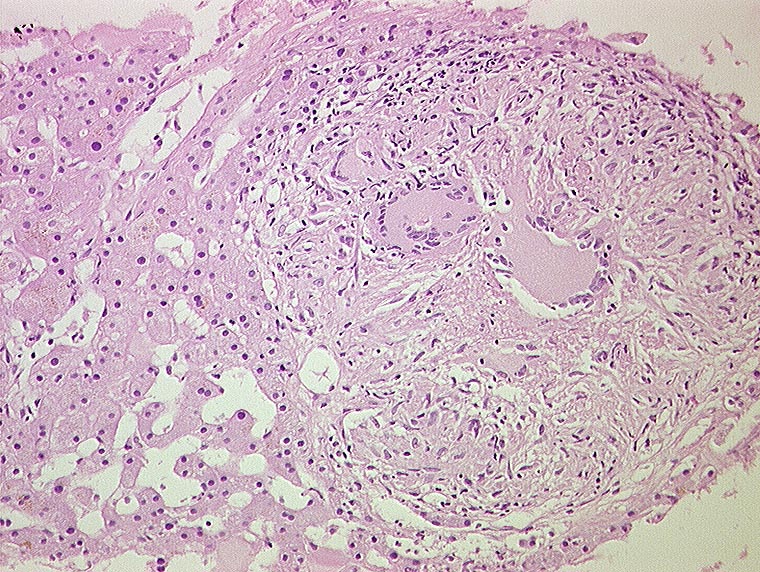

Miliartuberkulose : produktives Granulom

Nicht verkäsendes produktives Granulom aus Epitheloidzellen und Langhans'schen Riesenzellen mit hufeisenförmig angeordneten Kernen.

Histologie